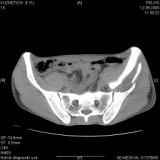

Уважаемые коллеги! Хотелось бы услышать совет по тактике лечения представлленого больного.Поступил после лечения в одном изотделений области. Травма 2,5 месяца назад. После выведенияиз шока был произведен остеосинтез перелома бедра, предплечья, до перевода к нам проводилосьвытяжение по оси шейки бедра за стержень, введенный в большой вертел. На сегодня деформацияригидна, клинически мобильности не определяется. Заранее признателен. P.S. Данный вид травм не включен в перечень "высокотехнологичных операций", направить длялечения по квотам Минздрава очень сложно.

Это обзорные и косые снимки

С уважением,

Leonid

Привет, Леонид. Оскольчатый высокий двухколонный перелом в такие сроки трогать не надо, т.к. это про такие переломы сказано: "кто с ножом на Ж. пойдет тот в ней и останется...".